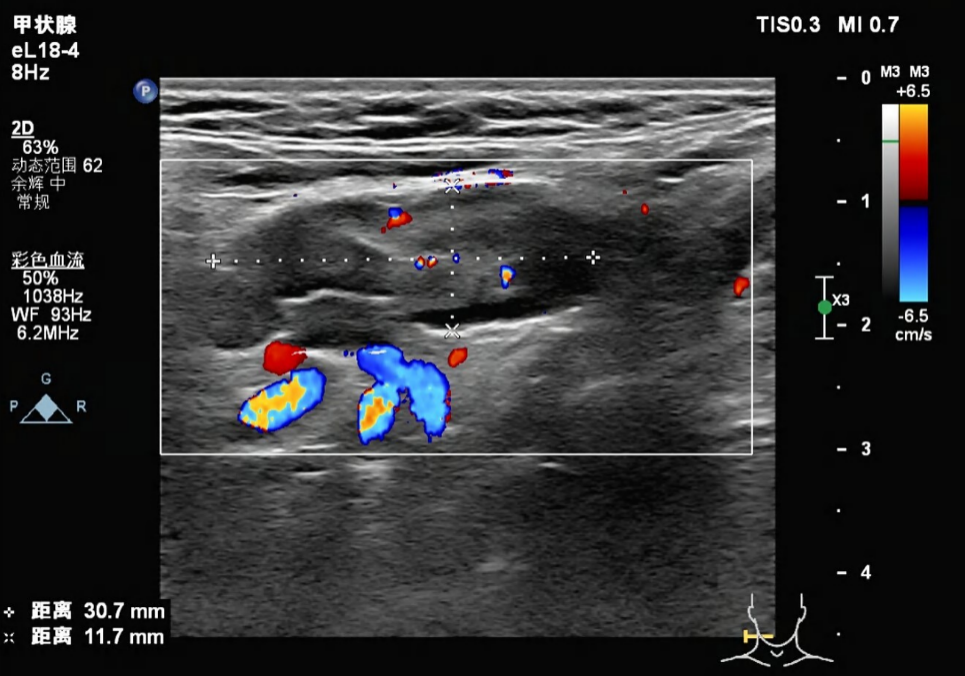

甲状腺彩超:甲状腺实质回声欠均匀。